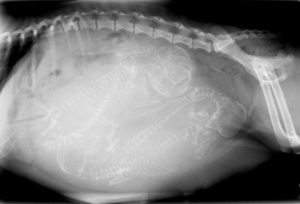

At California Dog & Cat Hospital in Stockton, CA, we are proud to be able to offer digital x-rays and telemedicine capability. Radiology is a technique and diagnostic tool we use to look inside the body in an entirely non-invasive way. X-rays allow us to create images of the body’s organs. In other words, the use of radiology gives us a view of the internal organs in your pet’s body that we otherwise could not see. It’s a valuable diagnostic tool that helps veterinarians detect and prevent illnesses.

The images produced by digital radiography are able to obtain without having to have traditional films developed. The radiographs can be manipulated digitally, giving us the best possible radiographic information to help us diagnose your pets. Radiographs (x-rays) can be such an important tool in cases ranging from vomiting to limping on a back leg. In some cases x-rays are not helpful then we would need other advanced imaging to help guide us in our treatment plan.